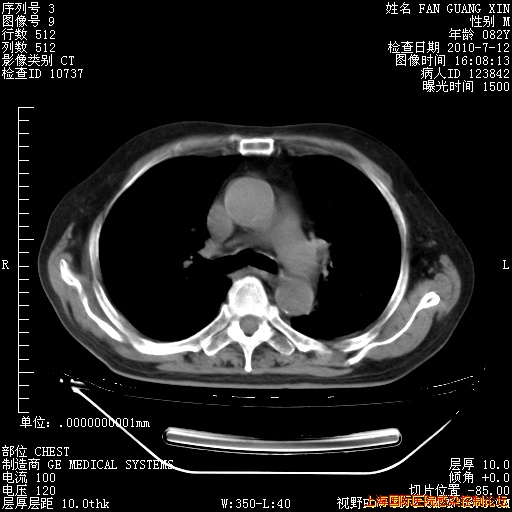

补发6月12日肺部CT肺窗

6月12日肺窗